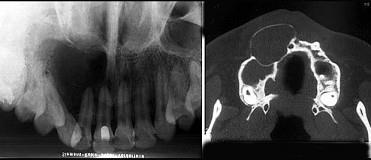

位于上颌侧切牙与尖牙之间的非牙源性囊肿(影像检查如图)是 ( ) A.球上颌囊肿 B.正中囊肿 C.鼻唇囊肿 D.鼻腭囊肿 E.角化囊肿

选项 A.球上颌囊肿 B.正中囊肿 C.鼻唇囊肿 D.鼻腭囊肿 E.角化囊肿

答案 A